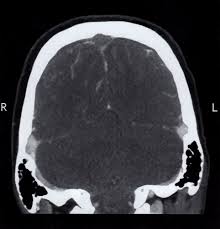

The superior sagittal sinus is most often. An obstruction resulting from venous thrombosis in dural/cortical veins or a venous sinus (fig. We received 32 patients hospitalized on. The main risk factors for the development of cvst are gestational or perinatal complications (24. People who have had any type of stroke recover best if they get treatment right away.

Cvst is rare and characterised by thrombosis of the dural sinuses and cerebral veins, causing venous congestion, cerebral oedema, haemorrhagic venous infarctions, and neuronal damages. The most frequent and often early symptom of thrombosis of cerebral veins and sinuses is a headache. This condition may also be called cerebral sinovenous thrombosis. Cerebral venous sinus thrombosis incidence is higher than previously thought: Its risk factors include hypercoagulability of various causes.

The cerebral venous and sinus thrombosis (cvst), severe neurological emergencies is an important pathology of the venous brain system. The superior sagittal sinus is most often. Cerebral venous sinus thrombosis incidence is higher than previously thought: Living with cerebral venous sinus thrombosis. For this reason, it seems to be overlooked not only by general practitioners but also in some specific cases by neurologists as well.1. This prevents blood from draining out of the brain. Symptoms of cerebral venous sinus thrombosis may vary, depending on where the blood clot is. The patient was treated with lovenox, as well as thrombolysis using tpa. Cvst is a rare form of. Mayte sánchez van kammen, erik lindgren, suzanne m. Severe dehydration after competitive sport had induced cvst. Venous infarction caused by cerebral venous sinus thrombosis (cvst)9. The diagnosis of cerebral venous sinus thrombosis (cvst) was suspected.